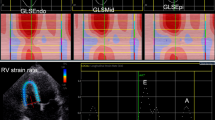

The two-dimensional speckle tracking echocardiography (2D-STE), as noninvasive ultrasound imaging technique was used for an objective and quantitative evaluation of global and regional myocardial function. The recordings with a frame rate between 50 and 70 frames/s were performed and analysed offline using General Electric software (EchoPAC software version 113 GE Medical Systems). Standard 2D gray-scale images of the LV were acquired at apical four-, two-chambers and apical long-axis view (Fig. 1), as well as parasternal short-axis view at base (mitral valve), papillary muscles and axis level. Global longitudinal LV myocardial strain (GLS) and systolic longitudinal, circumferential and radial strain were calculated offline. Longitudinal, circumferential and radial strain is analyzed on the 18-segment segmentation model. However, radial strain was not further processed because of a problem using 2D acquisition methods or a low number of high-quality images and suboptimal tracking which influenced the consistency of findings. Multilayer longitudinal and circumferential strains were determined by 2D-STE software which automatically creates a region of interest, which contained subendocardial (Endo), mid-myocardial (Mid) and subepicardial (Epi) layers (Fig. 2). Multilayer longitudinal strain was assessed in apical four-chamber, two-chamber and long-axis views, whereas multilayer circumferential strain was evaluated in the short-axis at the three levels as mentioned [18]. In randomly selected 15 patients, 2–4 weeks after performing the initial measurements, strain analysis was repeated by the same observer (G.K.) to determine intra-observer reproducibility. The absolute difference between two measurements divided by the average value of these two measurements was calculated together with interclass correlation coefficient (ICC).

Multilayer longitudinal and circumferential strains determined by two-dimensional speckle tracking echocardiography (2D-STE) in diabetic patient with acute hyperglycemia. a Subendocardial (Endo), mid-myocardial(Mid) and subepicardial(Epi) layers of longitudinal strain assessed in apical long-axis views; b Endo, Mid and Epi layers of circumferential strain at base (mitral valve) evaluated in parasternal short-axis view